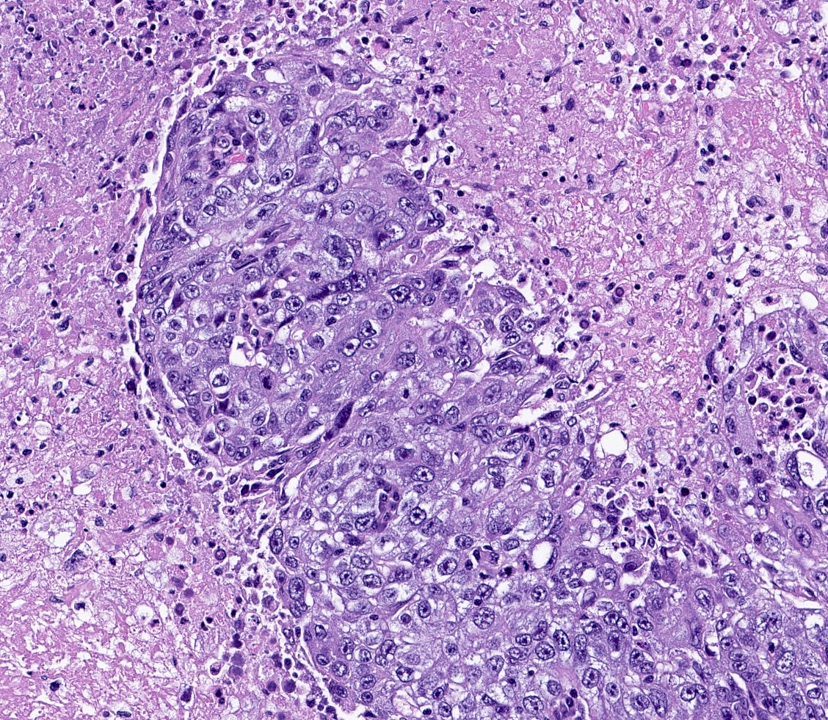

- Basal-like: high grade IDC, NST, solid tumor growth with pushing borders, geographic necrosis, nuclear pleomorphism, brisk inflammatory infiltrate, high mitotic index, high Ki67

- Most express basal cytokeratins (keratin 5/6, 14, 17) and EGFR

A 67 year old woman underwent a partial mastectomy for a breast tumor shown in the image. Microscopic sections revealed a high grade invasive ductal carcinoma growing as a solid mass with pushing borders, areas of necrosis, brisk mitoses and abundant tumor infiltrating lymphocytes. The tumor was negative for ER, PR and HER2 and was classified as basal-like by gene expression profiling. What other immunostain(s) might be positive?

B. EGFR. Basal-like breast cancers are typically high grade invasive ductal carcinoma of no special type that show solid tumor growth with pushing borders, geographic necrosis, nuclear pleomorphism, a brisk inflammatory infiltrate, a high mitotic index and a high proliferative index with Ki67. Most basal-like breast cancers express basal cytokeratins (keratin 5/6, 14, 17) and EGFR. Answer A is incorrect because while a minor proportion of triple negative breast cancers can express androgen receptor, the prototypical AR positive breast tumor has apocrine features (apocrine carcinoma). Answer C is incorrect because KIT is not characteristically expressed in breast carcinomas. Answer D is incorrect because synaptophysin may be expressed in breast tumors with neuroendocrine differentiation, which typically cluster within the luminal category.